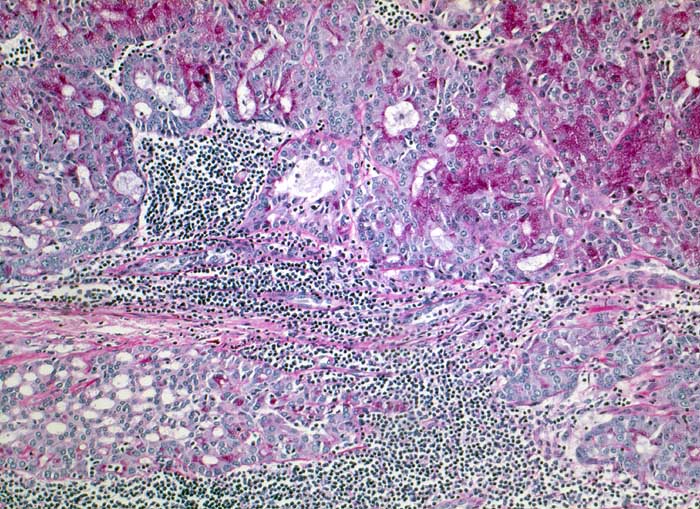

Azinuszellkarzinom der Glandula Parotis

Die zytologische Diagnose des Azinuszellkarzinoms basiert auf dem Nachweis von Azinuszellen bei gleichzeitigem Fehlen von Gangstrukturen. Die Tumorzellen gleichen normalen serösen Azinuszellen. Zytoplasma ist reichlich vorhanden und variiert von schaumig bis grobgranulär. Degranulierte Zellen erscheinen schaumig, Zellen mit dichtgepackten Granula gleichen Onkozyten. Die Granula der Onkozyten sind aber feiner. Die Tumorzellkerne sind meist ziemlich wenig atypisch und monomorph. Das Chromatin variiert von fein bis mittelgrob. Intranukleäre Zytoplasmaeinschlüsse kommen vor. Die oft vorhandenen zahlreichen Nacktkerne müssen von ebenfalls oft vorhandenen Lymphozyten abgegrenzt werden. Die meist hoch differenzierten Tumoren können mit normaler Speicheldrüse verwechselt werden.